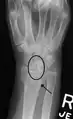

Static scapholunate dissociation

X-ray images indicate scapholunate ligament instability when the scapholunate distance is more than 3 mm, which is called scapholunate dissociation.[7] A static scapholunate instability is generally readily visible, but a dynamic scapholunate instability can only be seen radiographically in certain wrist positions or under certain loading conditions, such as when clenching the wrist, or loading the wrist in ulnar deviation.[6]

In order to diagnose a SLAC wrist you need a posterior anterior (PA) view X-ray, a lateral view X-ray and a fist view X-ray.[8] The fist X-ray is often made if there is no convincing Terry Thomas sign. A fist X-ray of a scapholunate ligament rupture will show a descending capitate bone. Making a fist will give pressure at the capitate, which will descend if there is a rupture in the scapholunate ligament.